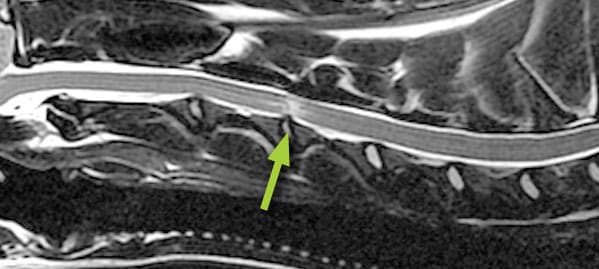

The spine is made up of individual bones (vertebrae) separated by discs. These discs act as cushions, absorbing shock and allowing for movement. Traumatic disc extrusion occurs when a sudden, forceful impact causes the soft inner core of a disc to rupture and completely extrude (leak out) from its normal position. This can put significant pressure on nearby nerves, causing pain and other neurological symptoms.

Diagnosing traumatic disc extrusion often involves a combination of tests, including: